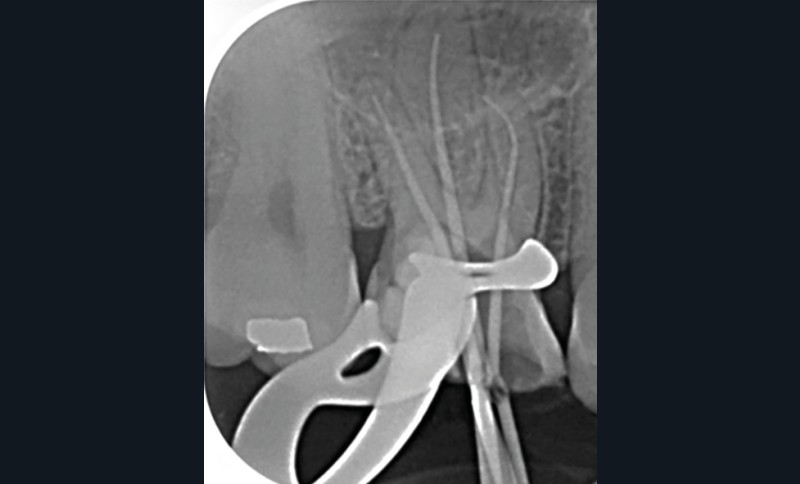

13. si possible, mise en place d’un champ opératoire sur la dent concernée, de sorte à isoler la zone de perforation de toute humidité (fig. 2) ;

14. mise en forme de la zone de perforation à l’aide d’inserts ultrasonores afin d’obtenir des bords nets et en supprimant les parois trop fines ;

15. mise en place du matériau selon le protocole lié au biomatériau utilisé, il est important de reproduire la morphologie de la dent et de veiller à obtenir un état de surface optimal ;